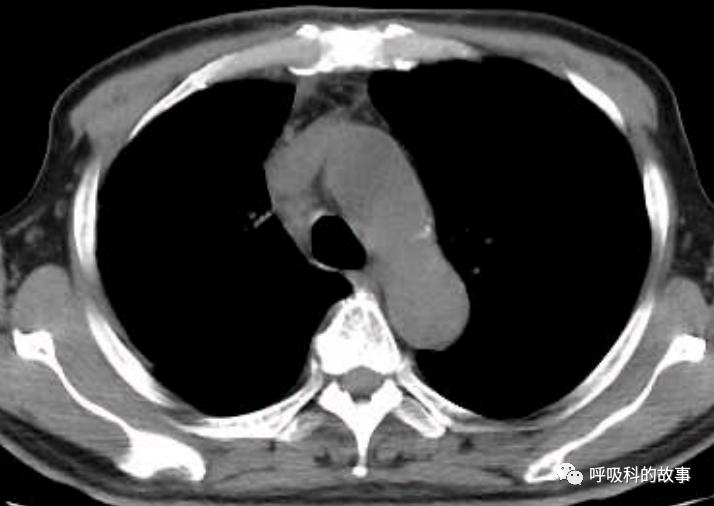

当然,需要鉴别的疾病主要是结核导致淋巴结肿大(见下表),可以发现结核淋巴结肿大多是中央低密度和不均匀低密度区,强化多为环状强化;而马尔尼菲感染的淋巴结肿大多是均匀密度,强化多为均匀强化。